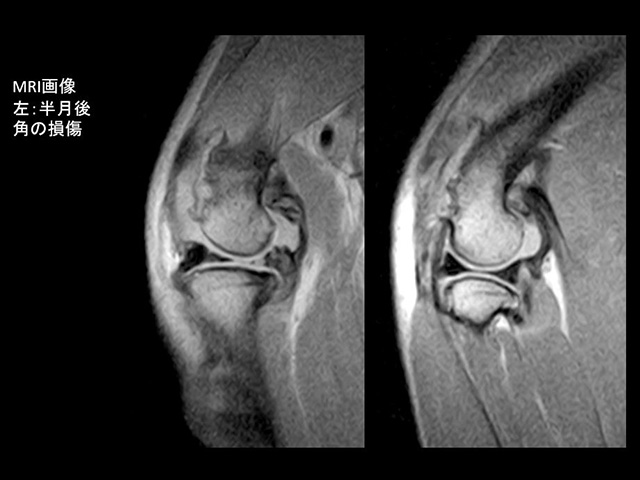

歴史的には、筋膜や靭帯の一部など自己組織を利用した関節内法や縫合糸などを使用して大腿骨と脛骨の動きを制動する関節外法が多く実施されてきましたが、使用組織や縫合糸の早期破綻、感染などの合併症が多く報告され、現在では脛骨骨切りによる機能的安定化手術が最良とされています。

中でもTPLO(Tibial Plateau Leveling Osteotomy; 脛骨高平部水平化骨切術)の成績が良好との研究報告が出され、世界的に広く認知されるようになっています。